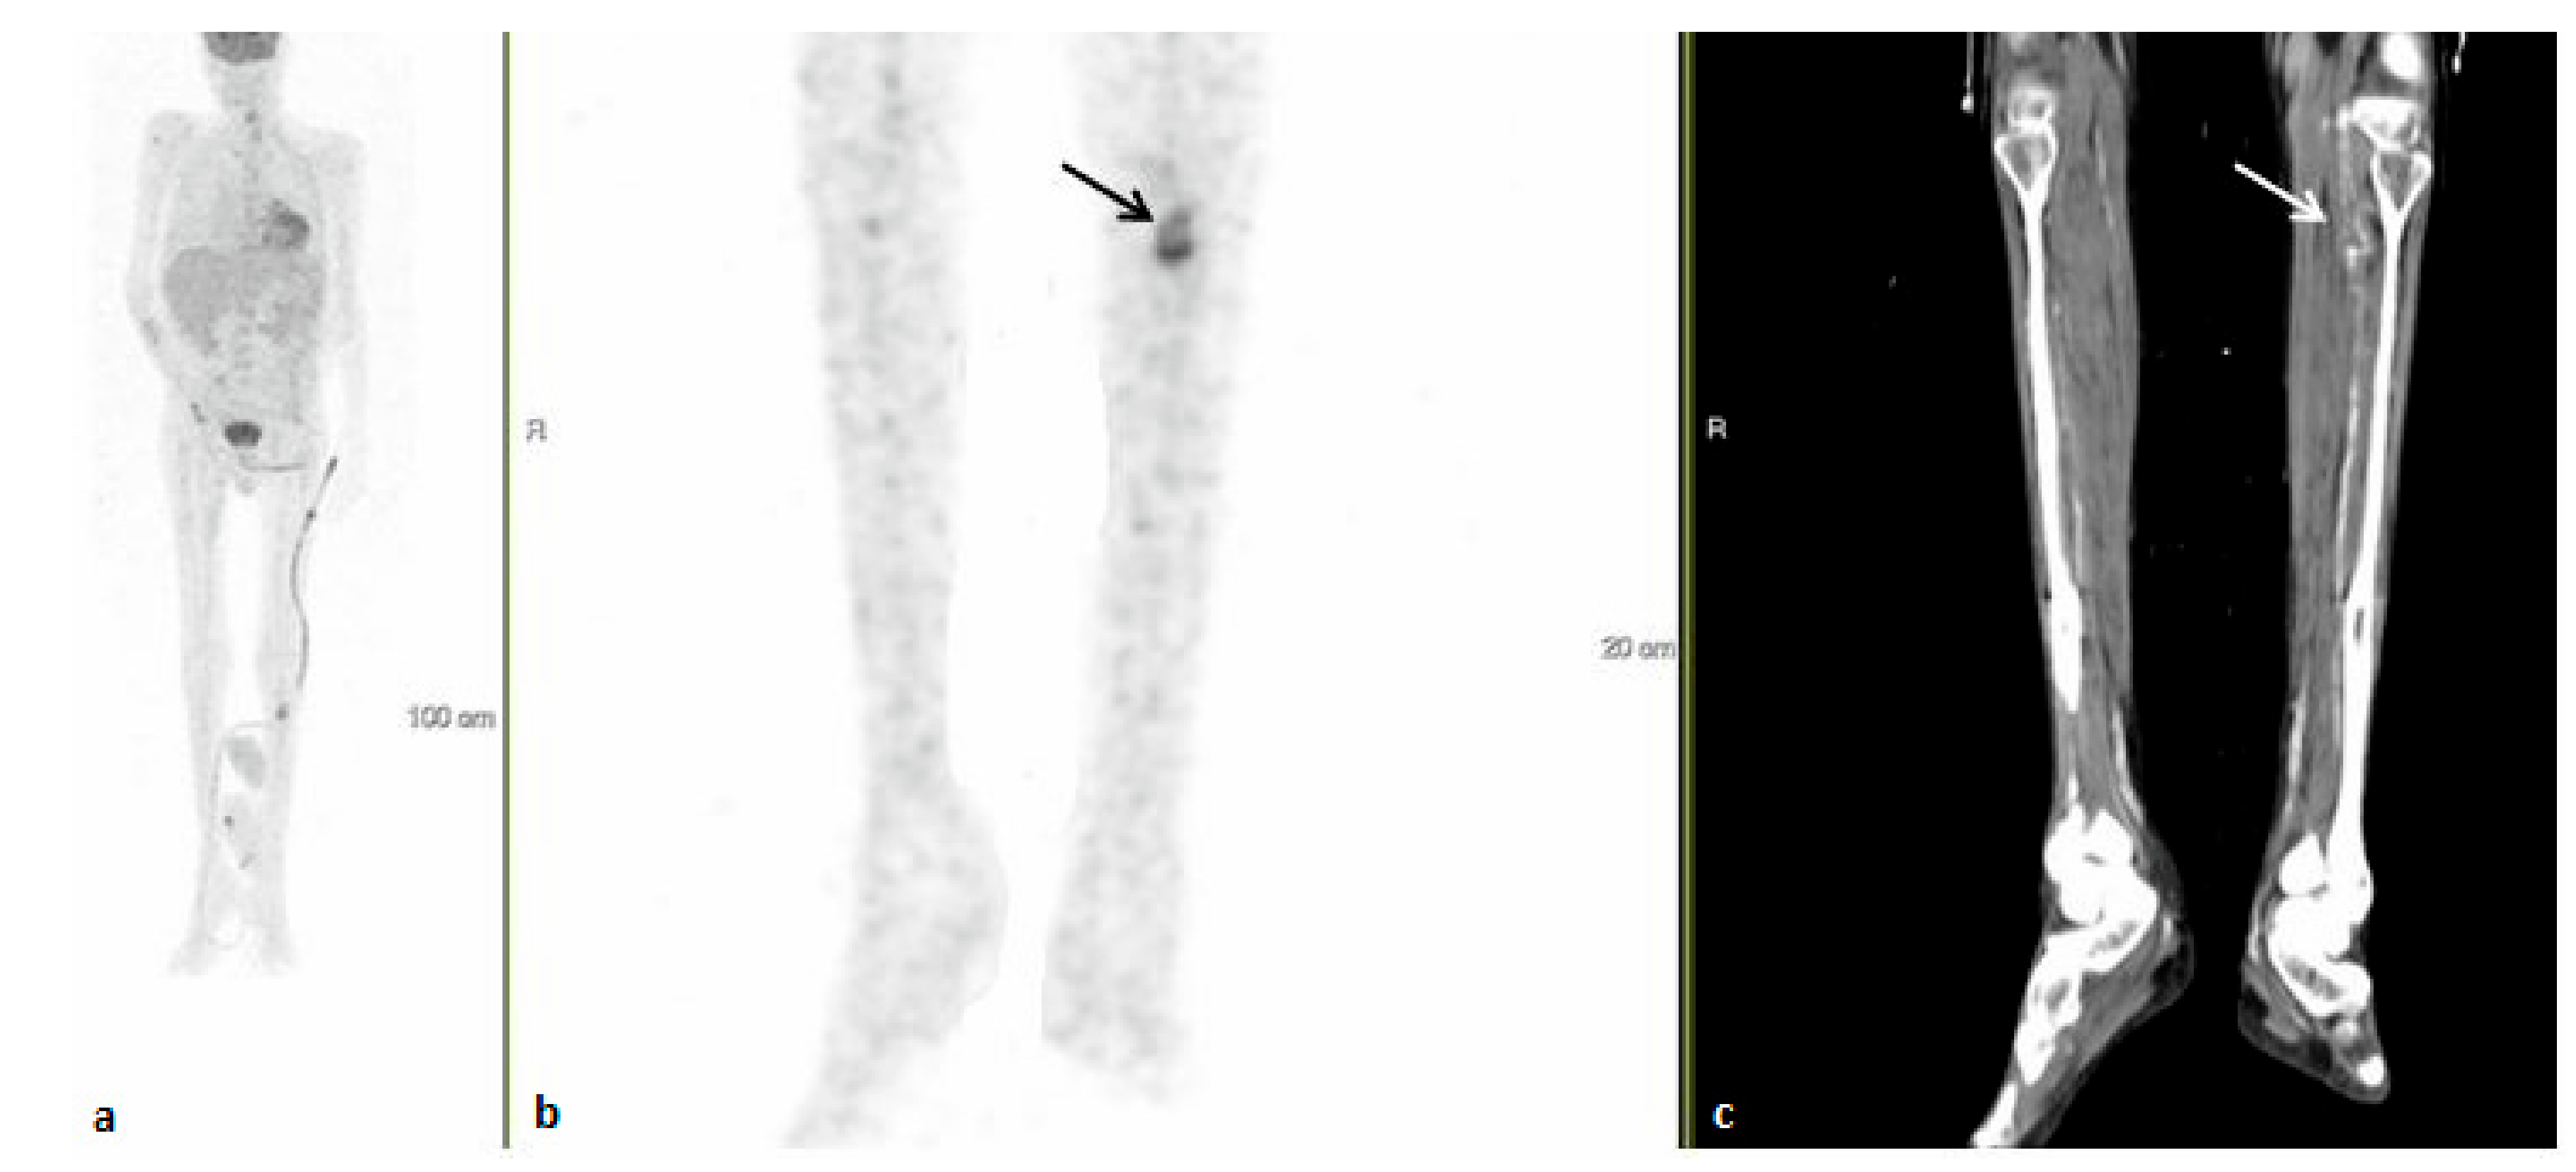

3.3. Contribution of 18FDG-PET/CT to FUO Workup

3.4. 18FDG-PET/CT Contributiveness According to Disease Category